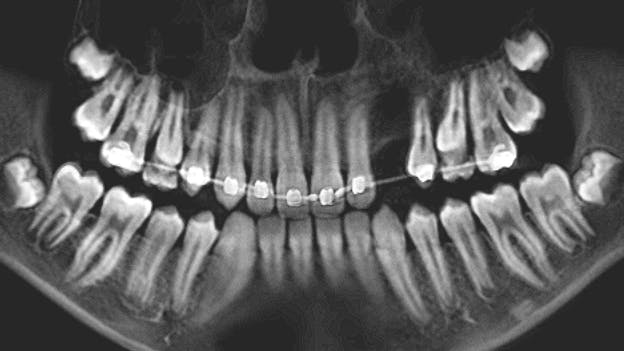

During her routine oral screening and exam, a 9 mm x 3 mm white leukoplakic patch of tissue on the left ventral surface of the tongue was noted. It was not tender to palpation, could not be scraped off, and the patient was unaware of its presence. It was recommended that the patient come back in two to three weeks to assess for continued presence.

The patient was referred to an oral surgeon where evaluation and an excisional biopsy were performed.